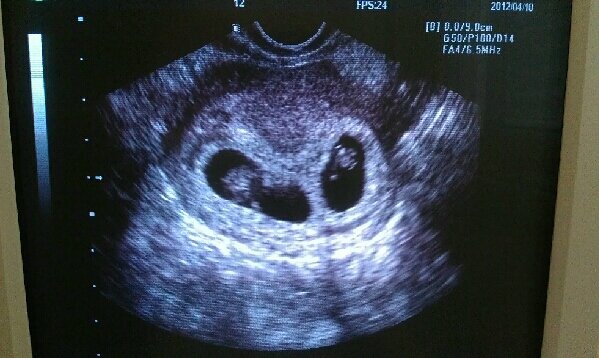

Ma hajnalban megfájdult a hasam. Inkább a gyomrom alatt éreztem, nem az alhasamban, de nagyon megijedtem. Reggel elmentem a háziorvoshoz. Ő nem talált semmit, csak azt, hogy a gyomromból sugárzik ki a fájdalom. Valószínűleg a sok hányás és a kevés evés készítette ki a gyomromat. Felhívtam Paragit is, hogy nagyon aggódom nincs-e baja Törpikének, mikor tudna megnézni. Mondta hogy Százhalombattán rendel ma, menjek el oda. Hallottuk a baba szívhangját. :D Csodálatos volt. Nem találta miért fájhat a hasam, nem talált semmi gondot. A férjem szerette volna meghallgatni még 1x a szívhangot. Meghallgattuk, de Paragi olyan furcsán nézett és csinált egy hasi UH-t is. Majd ismét egy hüvelyit. Miután megemeltem a csípőmet a következő kép tárult elénk:

Kép

Szóval nem Törpike, hanem Törpikék. :lol: